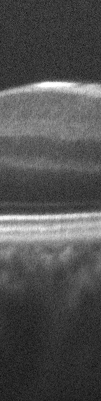

Fig. 4: A portion of one of the input images (a) and the results of ImageJ translation (b), ImageJ rigid (c) and RASL rigid registration based methods.